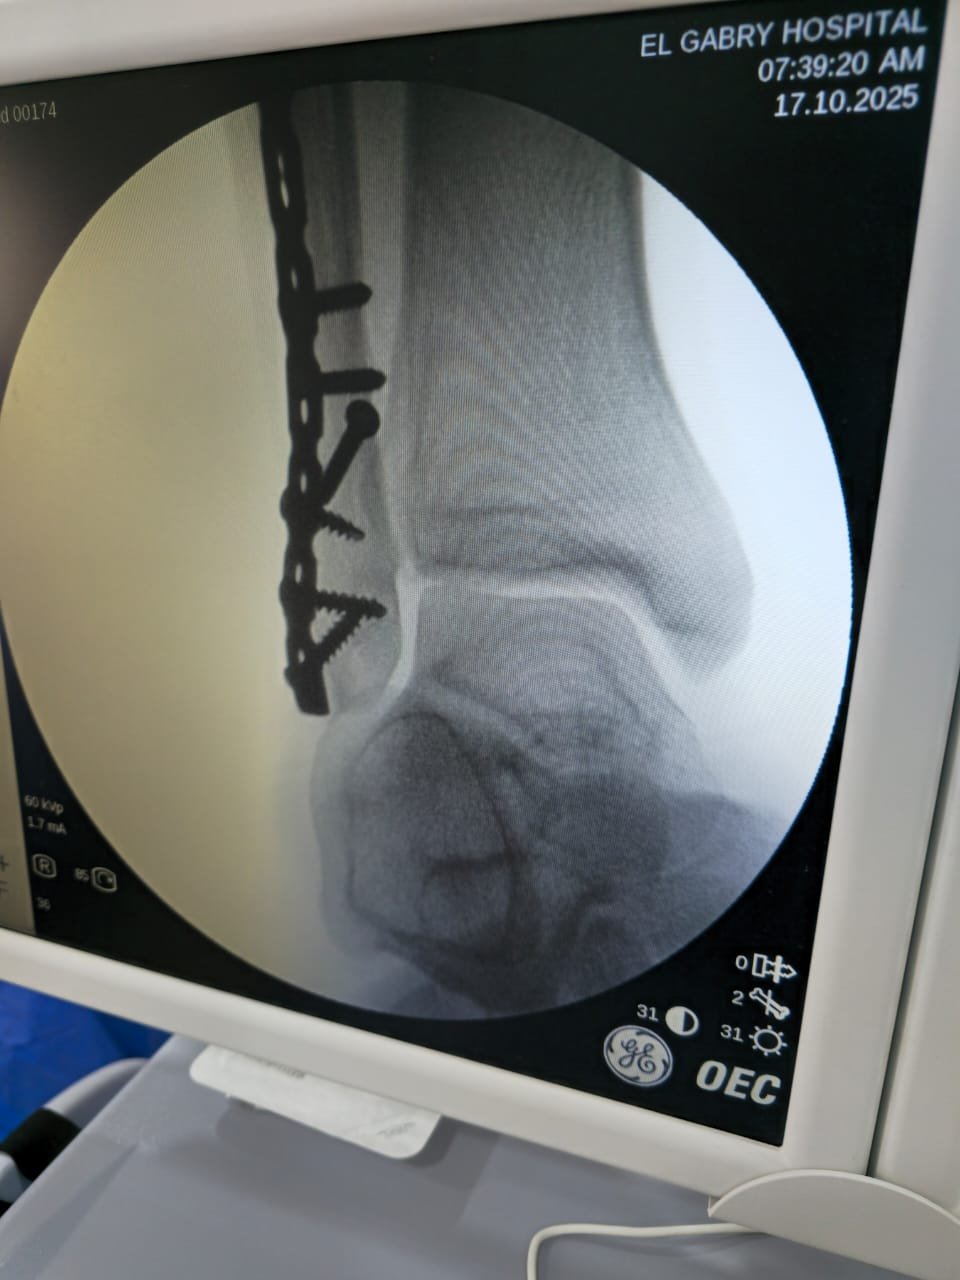

يحدد د. أحمد خطة التعامل مع الكسر أو الرضّ العظمي: فحص سريري وقراءة أشعة، اختيار التثبيت (جبس/جبيرة أو تثبيت جراحي عند اللزوم)، وضبط الألم، ثم متابعة منظمة حتى اكتمال الالتئام.

تشخيص سريع وقراءة أشعة دقيقة في نفس الزيارة.

مواعيد متابعة وصور توثّق تقدّم الالتئام واتخاذ قرار العودة للنشاط.